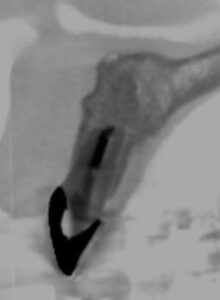

CT画像では顎骨は歯根を取り囲むように大きく吸収されており、嚢胞の完治は容易ではないことが推察されました。

そこで、治療は長期に及ぶことを説明し、「根管治療による嚢胞の縮小」⇒「外科的歯内療法による嚢胞の完全摘出」の2段構えの戦略を立てました。

治療期間は1年数か月に及びましたが、液体が溜まっていた嚢胞内部には骨が再生し、現在は治療後の経過観察を行っています。